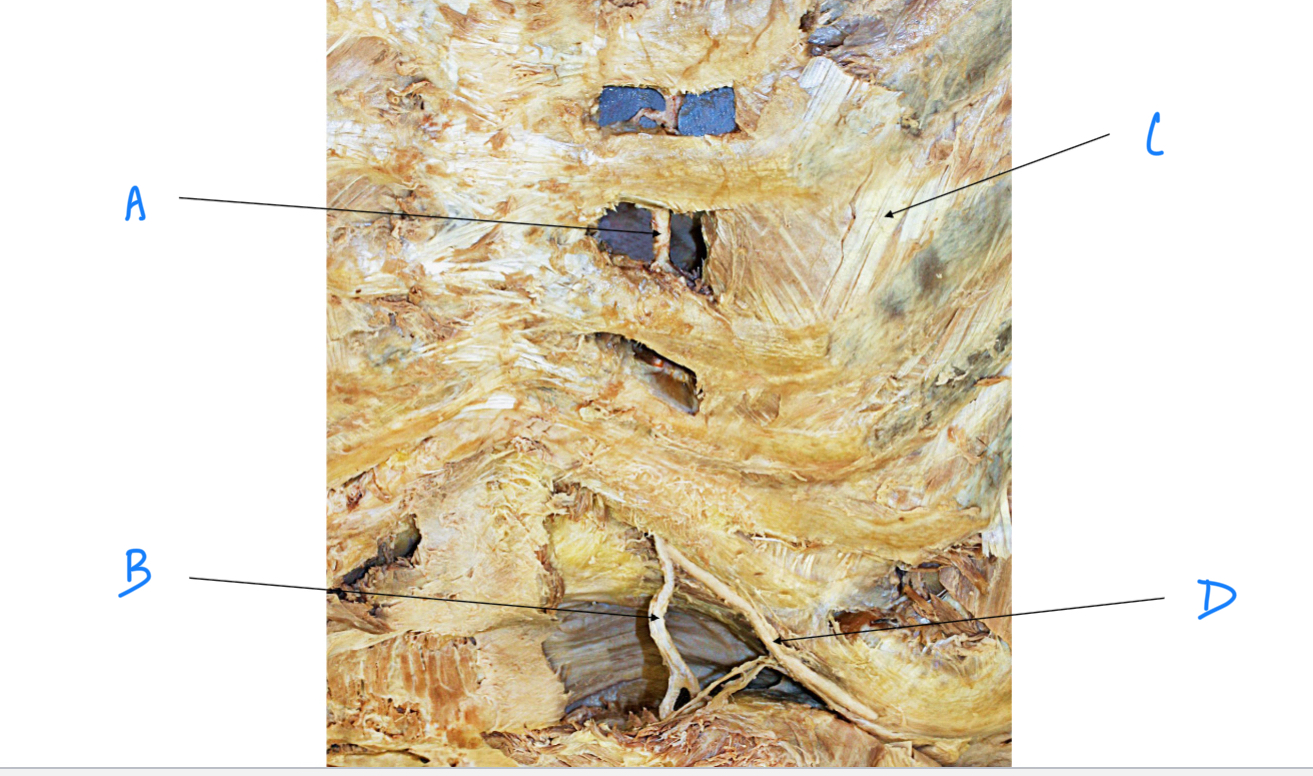

A. Identify structure

Transverse foramen; Vertebral a.

B. Identify structure; What goes through this feature?

Transverse process

C. Identify structure